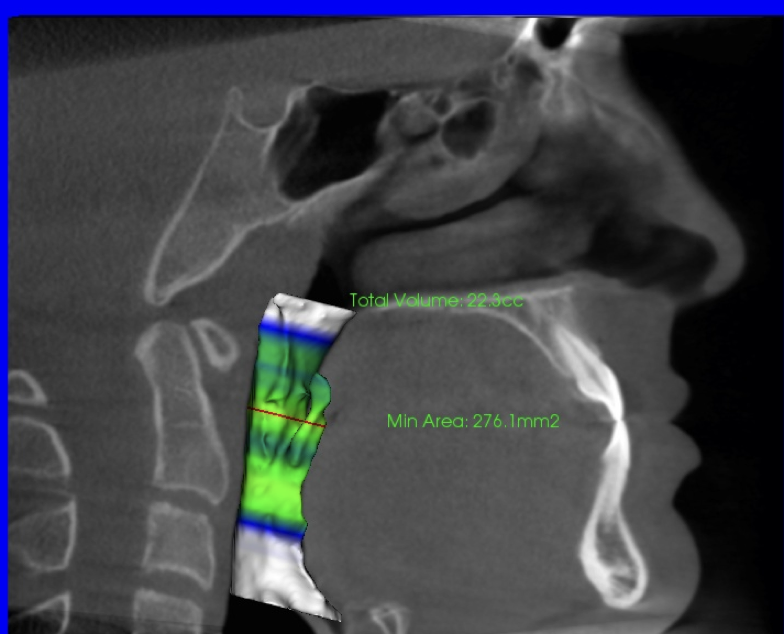

Case study: this patient’s airway volume increased after treatment with palatal expansion and lower jaw advancement

Before

After